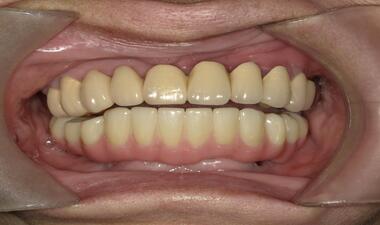

Full Arch術前術後 / 案例一

術後

裝戴固定下顎Full Arch假牙